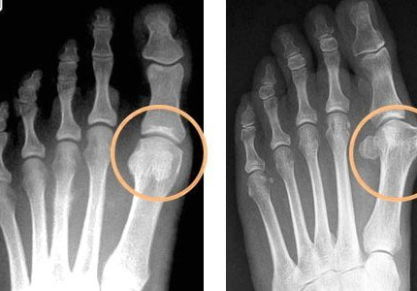

Подагра на ногах: лечение в домашних условиях народными средствами

Лечение подагры на ногах в домашних условиях. Причины и симптомы заболевания, медикаментозное и народное лечение подагры. Профилактика заболевания.